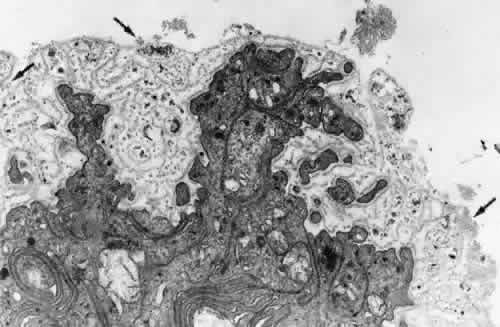

The ciliary zonular fibers originate in the pars plana as fine fiber bundles on the nonpigment epithelial basement membrane from 0.5 to 1 mm anterior to the ora serrata. They stain incompletely in gross specimens due to the overlying vitreous gel, narrowing to thin fibers as they near the ora (Fig. 9). By electron microscopy most appear to originate as small fibers containing 5 to 10 or more fibrils, adherent to the basement membrane of the epithelial cells, some becoming incorporated in the redundant infolding of the multilaminar basement membrane that develops with aging (Fig. 10). Small bundles are sometimes found superficially between these cells with no intervening basement membrane. Microfibrillar bundles found between some pigmented epithelial cells near their bases and in and under their basement membranes37,46 have been suggested to be zonular but are more likely a mixture of the abnormal elastic microfibrils found in the pigment epithelium's aging basement membrane and/or related to inserting microfibrils from elastic fibers of the underlying ciliary body stroma.

Fig. 10. Attachment of zonular fibers to the ciliary epithelium of the pars plana. Small bundles (arrows) adhere to the surface and infoldings of the multilayeredepithelial basement membrane (TEM, × 17,000).